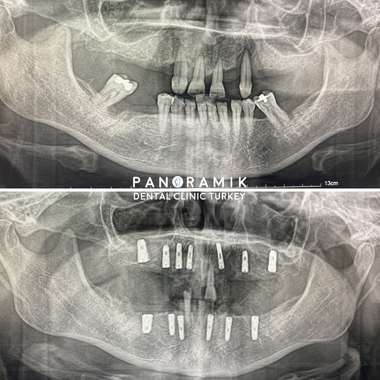

In the treatment of fixed implant or complete edentulism, the first examination is performed by your dentist. Then it is decided how many implants will be placed. At least 5 implants are placed, but this number varies according to the patient's systemic condition and bone level. The type of prosthesis is determined according to the number of implants. While 2-4 implants are used for removable prostheses, 5 or more implants should be placed for fixed prostheses.

In order to apply fixed prosthesis in edentulous patients, 7-10 implants are needed in the upper jaw and 5-7 implants in the lower jaw. In general, 8 implants are applied to the upper jaw and 6 implants to the lower jaw.